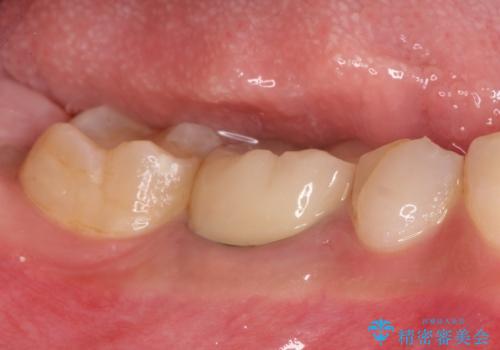

歯冠修復はオールセラミッククラウンで行なっております。